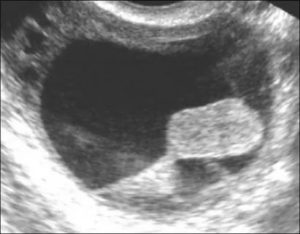

Обычно эти образования однокамерные и заполнены жировыми массами. Поскольку это герминогенная опухоль, в ней может содержаться жир, волосы, зубы или костная ткань, которые обычно находятся в солидном разрастании, выпячивающемся в полость кисты.

Ультразвуковая картина разнообразна — от диффузного эхогенного объемного образования до образования с солидными участками, выпячивающимися в просвет. Из-за большого содержания жира наблюдается дистальная акустическая тень.

В правом яичнике обнаружено однокамерное образование размерами 7 х 8 х 6 см, содержащее солидные участки, выступающие в ее полость.